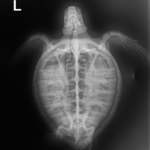

4.9 lbs. non -FP juvenile green

Patient Injuries

Entangled around the neck with braided fishing line

In-house PCV = 26 %, TP = 3.8 g/dl, glucose = 179. Started on Ceftaz, Vitamin B, Normosol and Meloxicam.